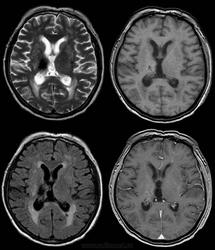

Непонятное сочетание Т1, Т2 и FLAIR

Через год после "инсульта", МРТ впервые.

Почему и на Т2 и на FLAIR - гипоинтенсивное, а на Т1 - не совпадает ни по форме, ни по структуре? Что это? Не кистозно-глиозные изменения и не гематома и все остальное, о чем я способен подумать.

Последствие кровоизлияния в проекции таламуса справа

Если сделать SWI (SWAN), то можно подтвердить наличие продуктов распада гемоглобина

тоже подумала об этом, слева определяется  щелевидной формы зона с аналогичными

как описать перивентрикулярные изменения? лейкоареоз?

Я написал лейкоареоз.